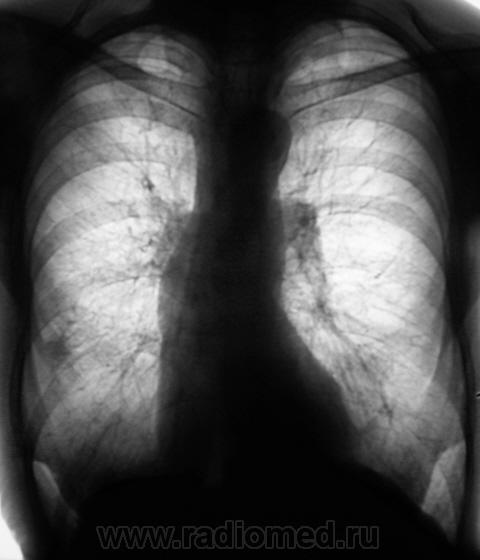

Флюорограмма за 2009 г.